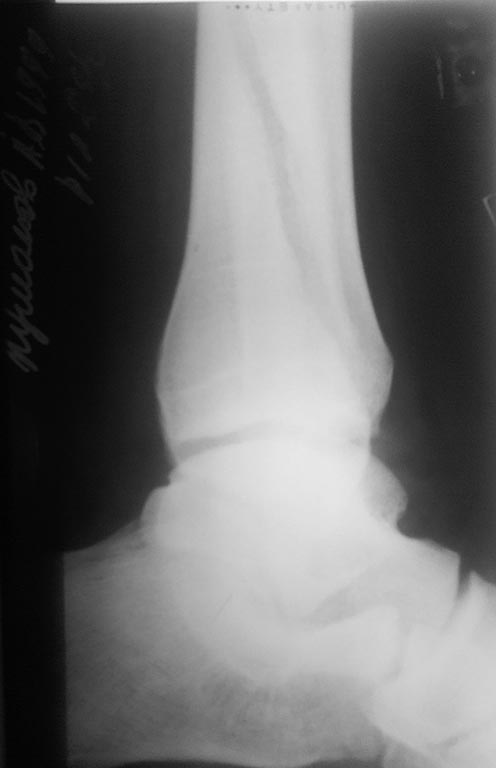

[Ortho] сохраняется подвывих?

пациент отказался. после операции прошло 3 дня, от момента травмы -

неделя. пациент ходит в гипсе без нагрузки на ногу. интересует, что

делать сейчас.

Вложение не в текстовом формате было извлечено…

Имя     : 2 ДП ПРЕТБГИ?И?2.jpg